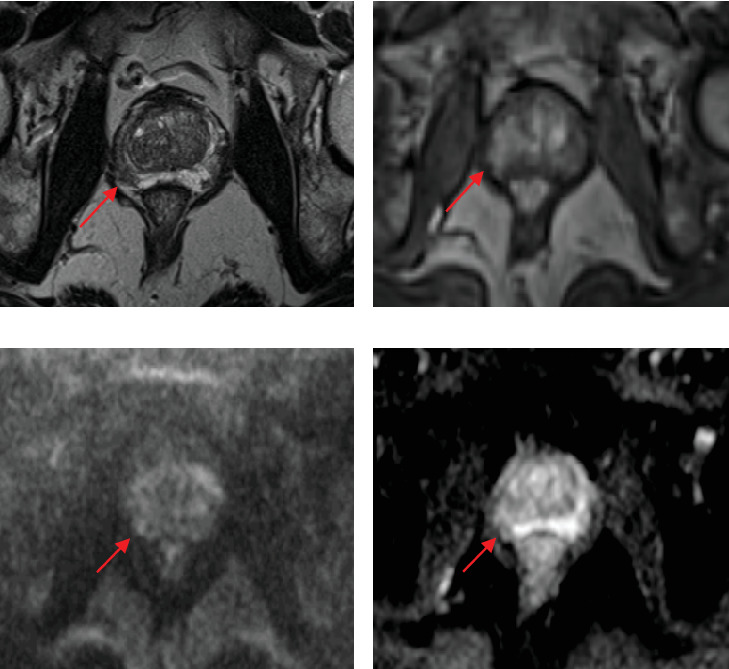

Patient selection for focal therapy (FT) of prostate cancer requires the assessment of MRI and biopsy results. However, there is currently little guidance for the utility of PSMA PET/CT in FT planning. We describe the case of a man originally considered an ideal candidate for FT based on biopsy and MRI who was found to have a contralateral lesion-harboring cancer detected only on PSMA PET/CT. Trial Registration: ClinicalTrials.gov identifier: NCT05852041.